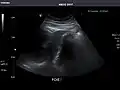

Liver

In patients with deranged liver function tests, ultrasound may show increased liver size (hepatomegaly), increased reflectiveness (which might, for example, indicate cholestasis), gallbladder or bile duct diseases, or a tumor in the liver.

Liver: Diffusely homogeneous and normal in echogenicity. No focal mass or contour nodularity. No intrahepatic biliary ductal dilatation.

Liver -